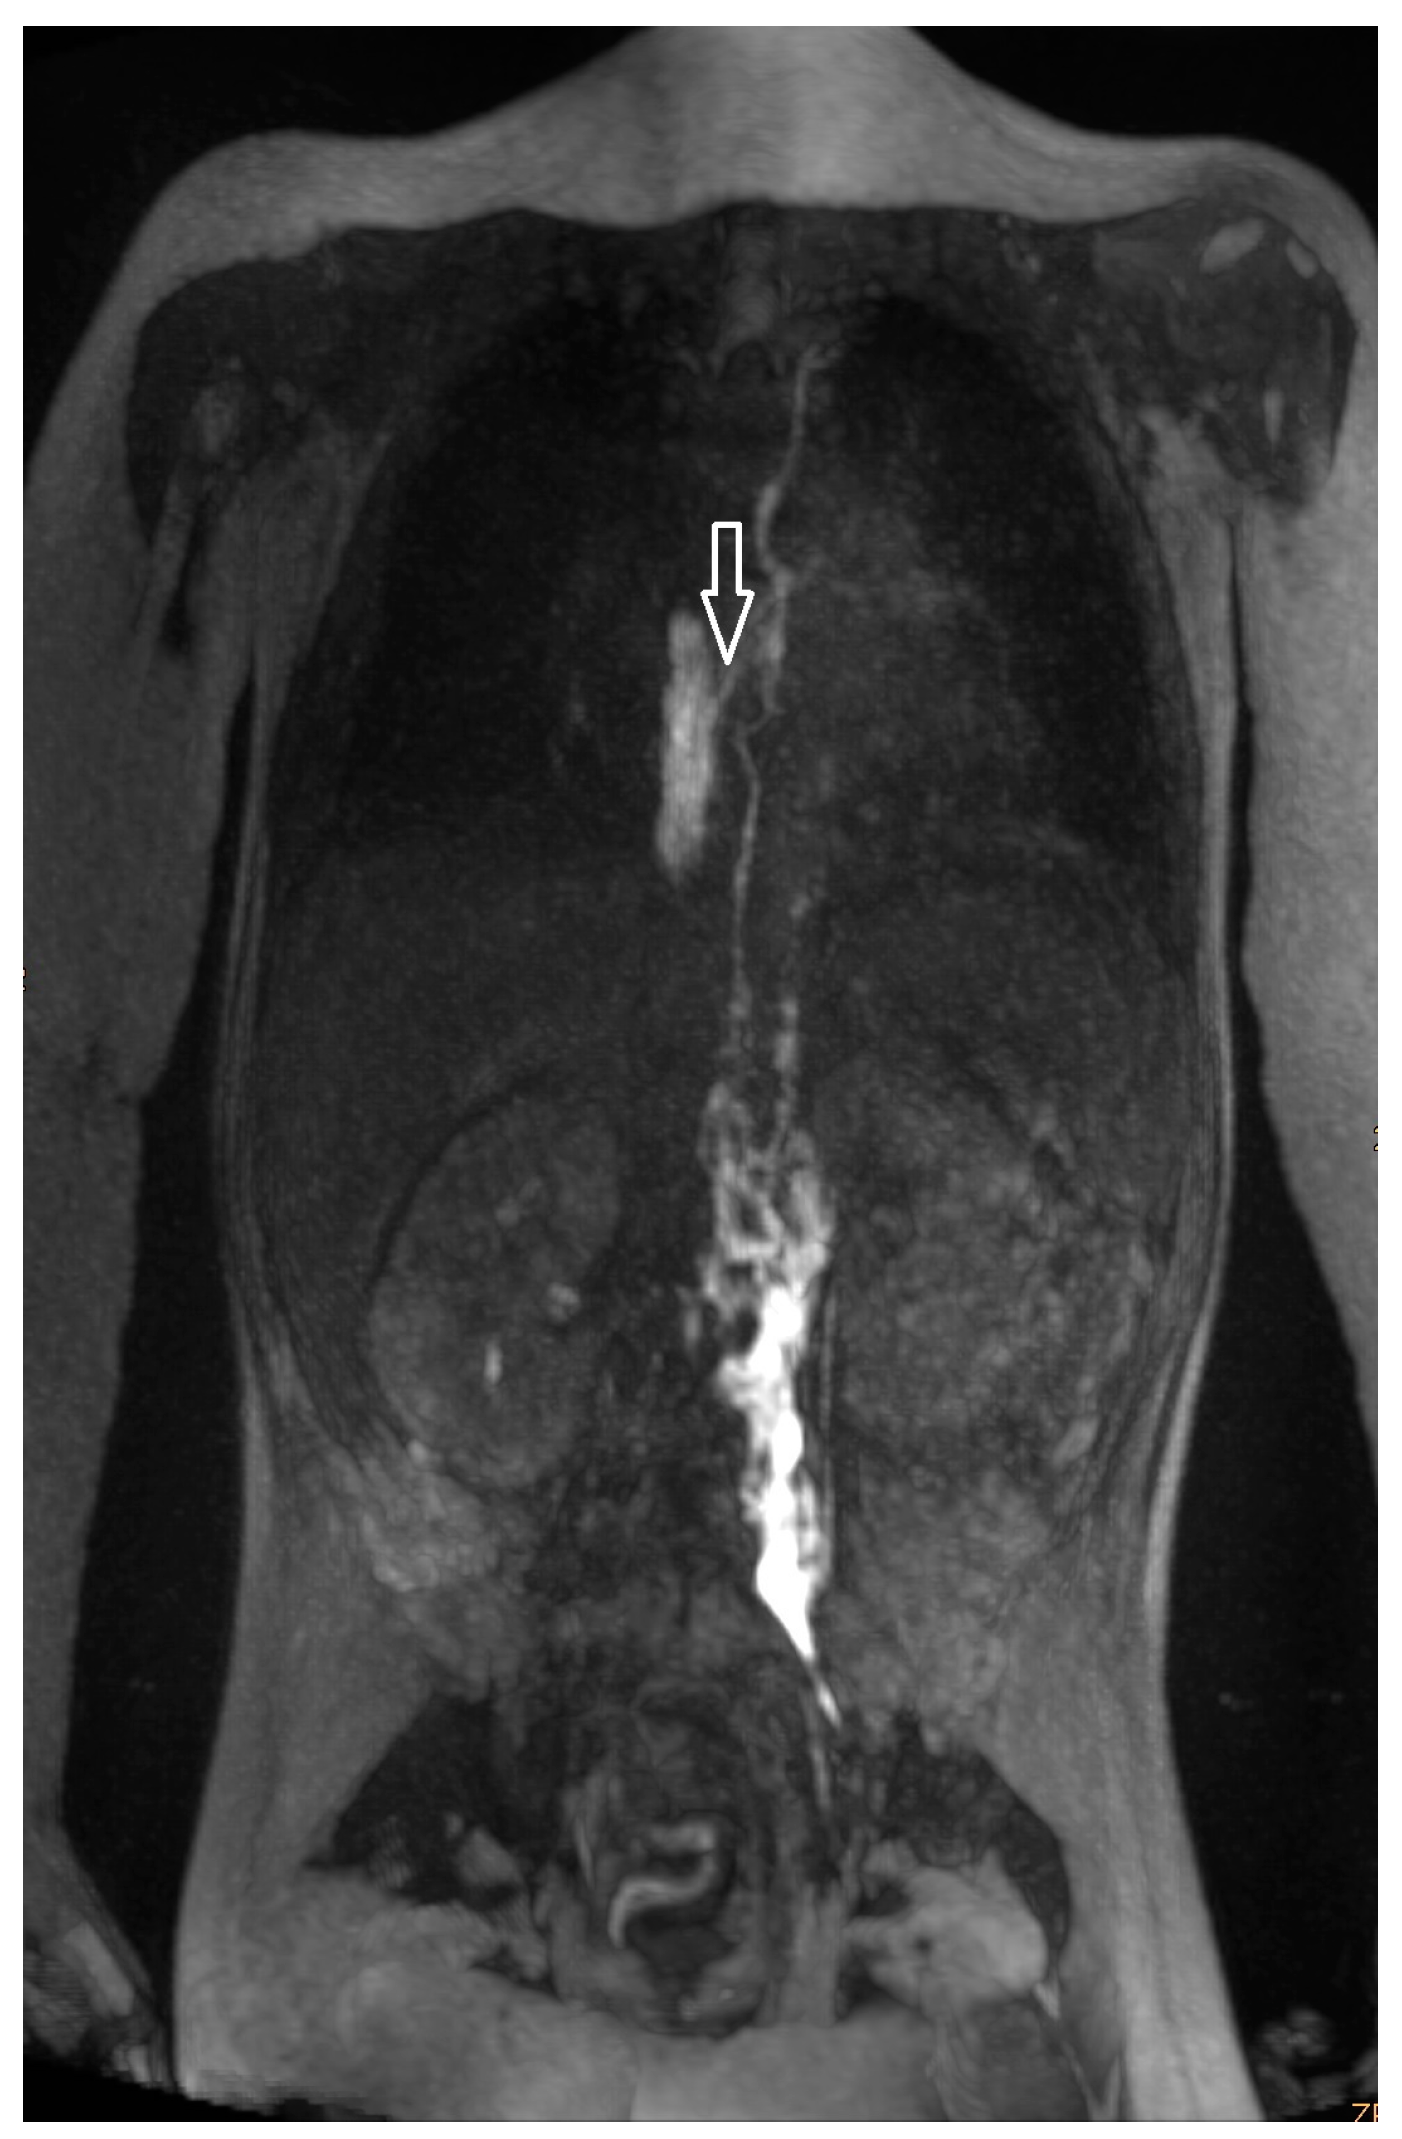

| 15 | 1 | increased signal neck le | TD intact, no retrograde flow | no | budesonide, sildenafil, macitentan, diuretics | no due to comorbidity | no improvement |

| 16 | 1 | increased signal neck le, hilar lymphadenopathy | TD intact, no retrograde flow | no | budesonide, macitentan, diuretics enalapril | glue embolization | albumin improved (FU 2 a 7 m) |

| 17 | 3 | increased signal neck and hilum | TD intact, no retrograde flow | no | budesonide, sildenafil, losartan | TD decompression | scheduled for transplantation |

| 18 | 1 | increased signal neck le | TD intact, no retrograde flow | no | budesonide, sildenafil, spironolactone | no (patient disapproval) | no improvement |

| 19 | 1 | increased signal neck le | TD intact, no retrograde flow | no | enalapril | no | transient improvement |

| 20 | 1 | slightly increased signal neck le | TD intact, no retrograde flow | no | enalapril, aldactone, budesonide | no | no improvement |